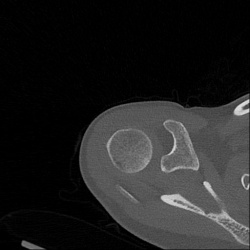

Женщина, 36 лет. Жалоб нет.

При флюорографии найдены тени в проксимальном метаэпифизе правой плечевой кости.

Кости смотрю редко. Заключился инфарктом.